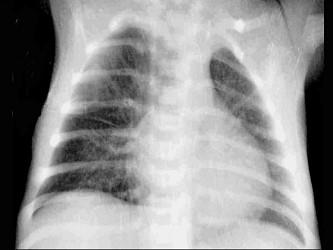

问题 4个月婴儿,因发热、咳嗽、气喘6天来诊。体格检查呈重病容,精神极度萎靡,皮肤有猩红热样皮疹,呼吸急促,三凹征明显,两肺散在中小水泡音,腹胀。实验室检查:血白细胞总数为26×10/L,淋巴80%,胸片示轻度肺气肿,见图,诊断应考虑 ( )

选项 A、肺炎双球菌肺炎 B、金黄色葡萄球菌肺炎 C、腺病毒性肺炎 D、支原体肺炎 E、急性毛细支气管炎

答案 B